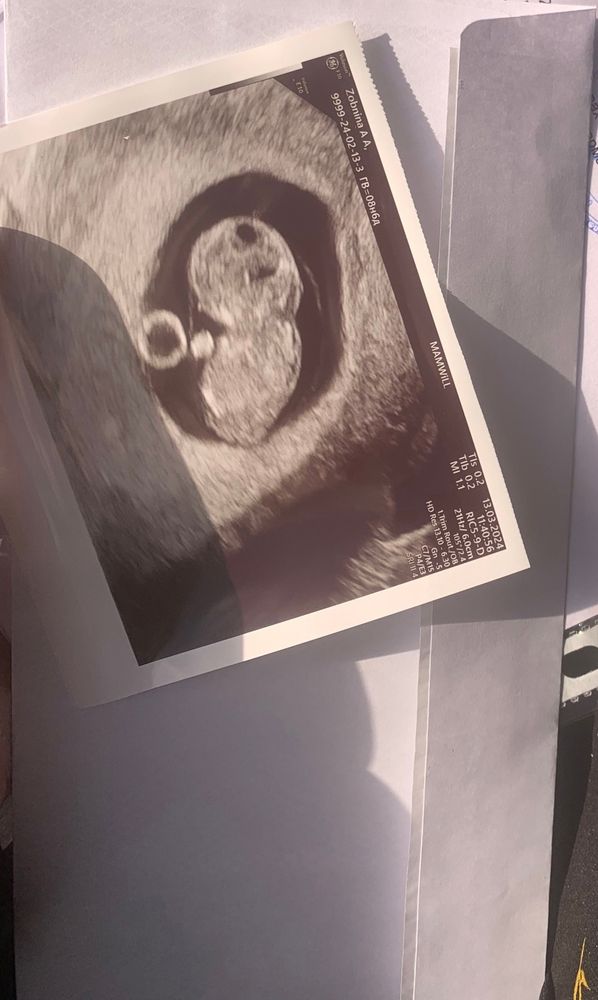

Узи 9 недель

На первых фото его видно, но главное размер.